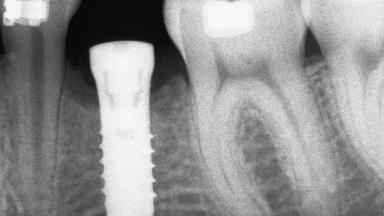

Autologous Block Graft and Guided Bone Regeneration (GBR) for Horizontal Ridge Augmentation in the Posterior Mandible

An 18-year-old man was referred for implant therapy in the posterior mandible to the Department of Oral Surgery and Stomatology (University of Bern, Switzerland). He was healthy and did not smoke. Tooth 35 was congenitally missing, involving a single-tooth edentulous space that offered an adequate mesiodistal dimension for implant placement but exhibited a typical pattern of buccal flattening. A panoramic radiograph was obtained, which revealed a sufficient vertical bone height above the mandibular canal and a normal bone structure in the edentulous area.

Bone Volume Deficient horizontally, requiring prior grafting